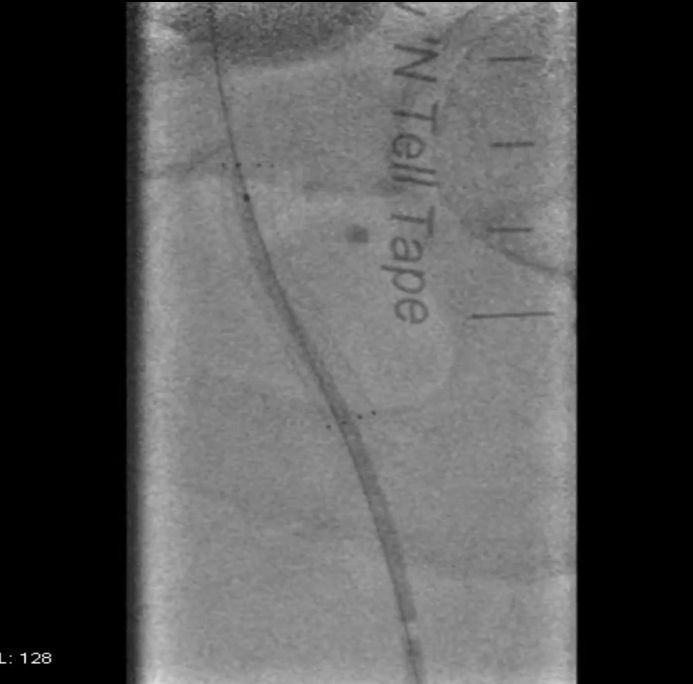

穿刺与造影定位

穿刺右侧股总动脉,置入8F翻山鞘,行左下肢动脉造影,可见左股浅动脉长段闭塞,远端流出道尚通畅。

既往支架已遮盖股浅动脉起始段